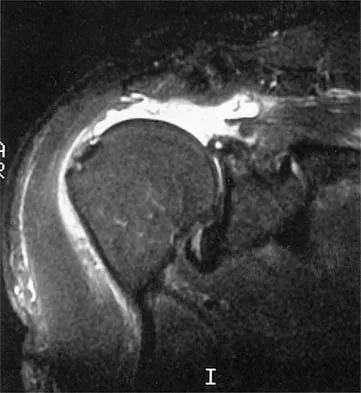

Figure 21 shows the radiograph of an 18-year-old man who was brought to the emergency department with shoulder pain following a rollover accident on an all-terrain vehicle. Examination reveals a fracture with massive swelling; however, the skin is intact and not tented over the fracture. Based on these findings, initial management should consist of

The radiographic and clinical findings suggest a scapulothoracic dissociation with a widely displaced clavicular fracture and a laterally displaced scapula. These injuries have a high association with neurovascular injuries to the brachial plexus and subclavian artery. Emergent vascular evaluation with arteriography and possible vascular repair are indicated. This repair can be combined with open reduction and internal fixation of the clavicle to improve stability. Delay in treatment of these vascular injuries can be devastating. Iannotti JP, Williams GR (eds): Disorders of the Shoulder. Philadelphia, PA, Lippincott, 1999, pp 632-635.